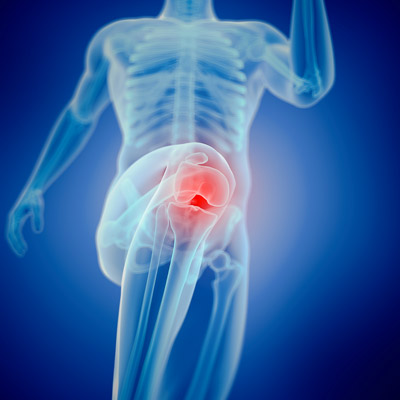

SOINS CLINIQUES DE POINTE

L’activité clinique est exercée de manière exhaustive au sein d’unités et d’équipes interdisciplinaires appliquant des protocoles et processus de qualité s’appuyant sur les meilleurs éléments scientifiques disponibles.

TECHNOLOGIE DE DERNIÈRE GÉNÉRATION

Nos professionnels croient en les équipements de pointe qui permettent des procédures d’intervention mini-invasives, ainsi que des procédures chirurgicales très complexes.